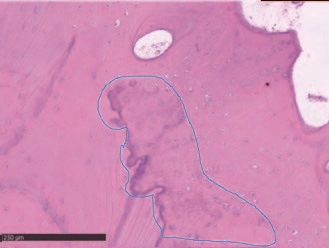

Гистологический анализ показал хорошо организованную, в основном зрелую ткань, образованную компактной пластинчатой костью с четко очерченными костными пластинками вокруг каналов Гаверсияна и Фолькмана, окруженных меньшими участками, в которых пластинки были менее организованными и богатыми остеоцитами на стадии созревания. Количество минеральной матрицы - от 69% до 72% - было особенно значительным. Воспалительного инфильтрата не наблюдалось.

Рис. 11 – Голубая область определяет участок с вероятным присутствием носителей, предполагает, что новая кость могла быть отложена именно из места трансплантации.